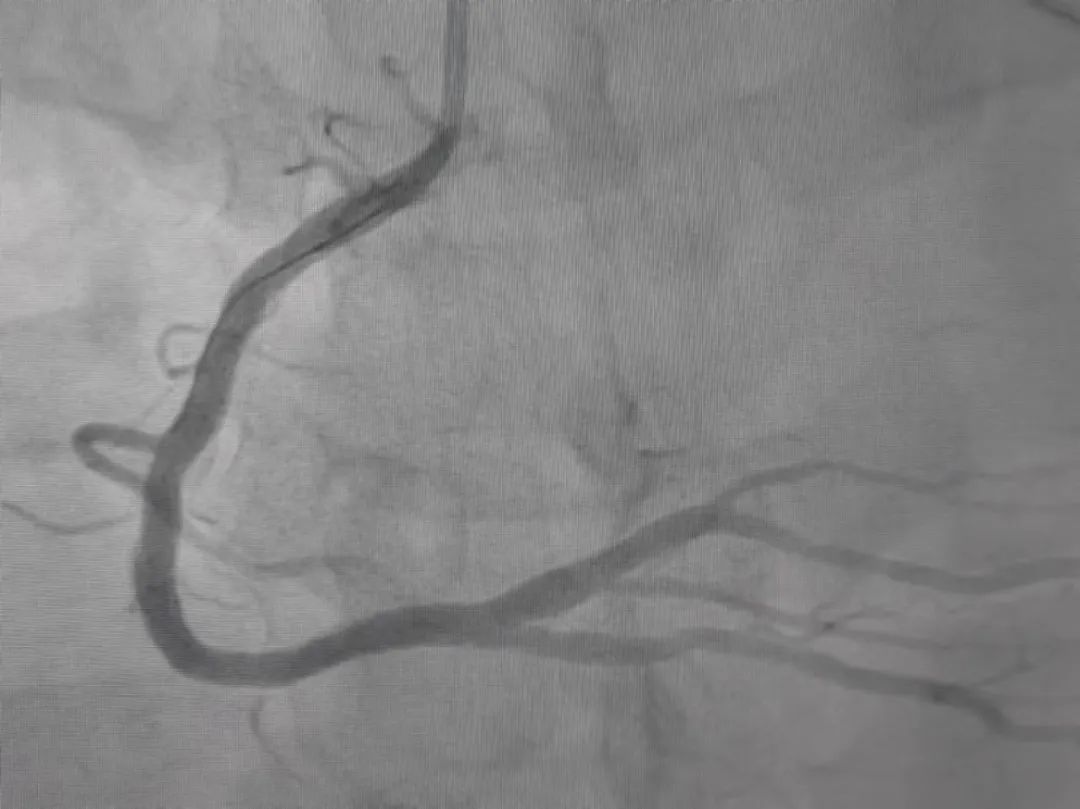

急性心肌梗死(AMI),是指冠状动脉闭塞,血流中断,使部分心肌因严重的持久性缺血而发生局部坏死。经急诊冠脉造影检查,发现小李的右冠状动脉被完全堵死了,情况十分危急。

△导丝穿过堵塞部位,打通了动脉

心血管内科团队第一时间就位,连夜展开抢救。手术中,梅益斌从梗塞部位抽吸出大块红色血栓,并成功植入一枚支架。经过抢救,小李胸痛等症状明显好转。经过几天的住院治疗,患者病情好转,已于日前康复出院。